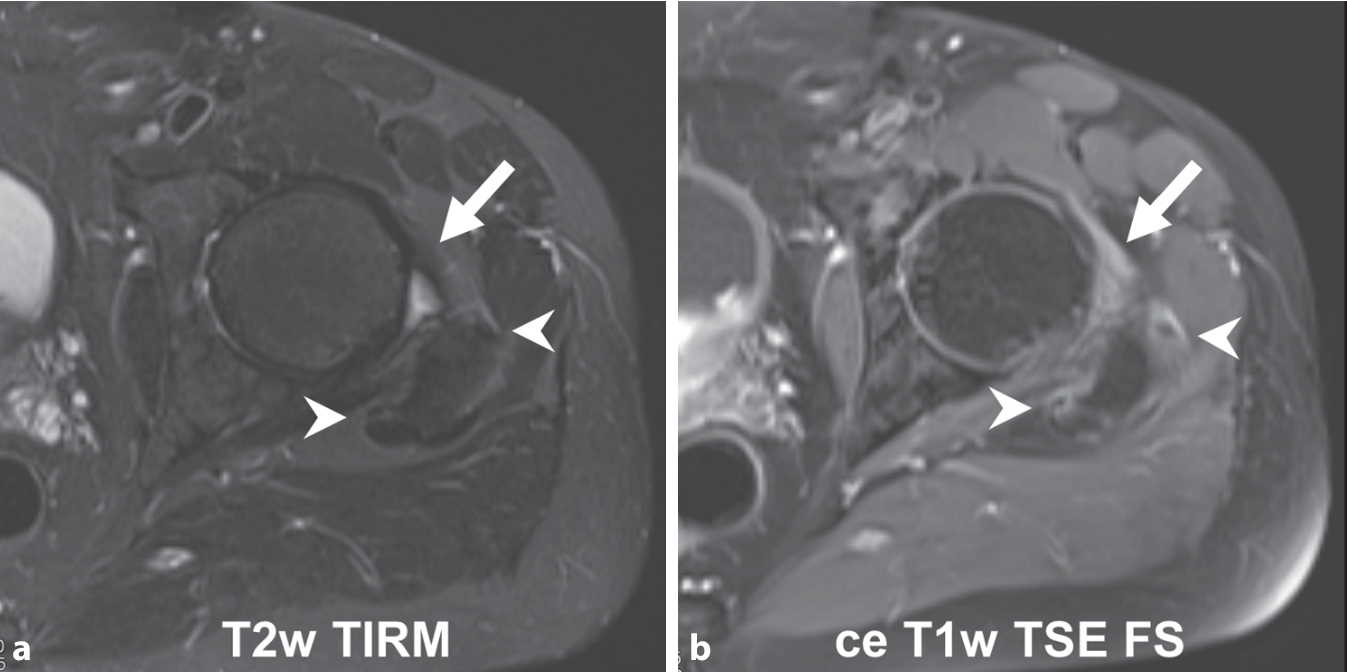

Based on our experience with PMR and MRI we observed that clearly detectable peritendinous contrast enhancement frequently correlates with only limited or even no peritendinous oedema (Fig. 1). Therefore, noncontrast-enhanced MRI scans are likely to underestimate the extent of inflammatory lesions with the consequence of misinterpretation of this finding.

Oedema-sensitive T2-weighted turbo inversion recovery magnitude (TIRM, a) and contrast-enhanced fat-saturated T1-weighted turbo echo spin (TSE FS, b) on the level of hip joint. Pericapsular inflammation (arrow) as shown by contrast-enhanced magnetic resonance imaging (ceMRI) lacks a correlate by oedema-sensitive imaging. Peritendinous inflammation around glutaeus medius and minimus tendons (arrow heads) correlate with only minute oedema, which can easily be overlooked